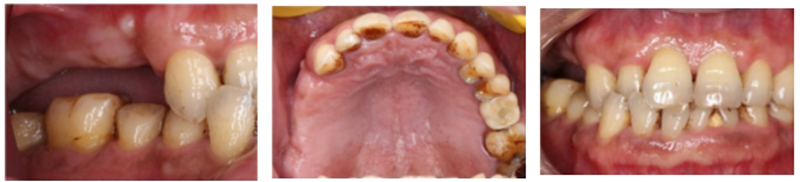

檢查:患者14、15、16、17缺失,無紅腫潰瘍,牙齦情況良好,口腔衛(wèi)生狀況良好。

診斷:14、15、16、17缺失

處理:通過數(shù)字化種植導航進行15、16、17種植修復